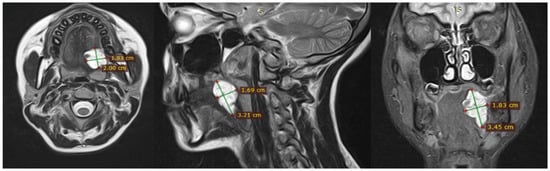

- A diagnosis of a venous malformation confirmed by radiological imaging (magnetic resonance imaging (MRI), CT, or ultrasound) and/or direct endoscopic visualization.

3.1. Magnetic Resonance Imaging (MRI) Findings